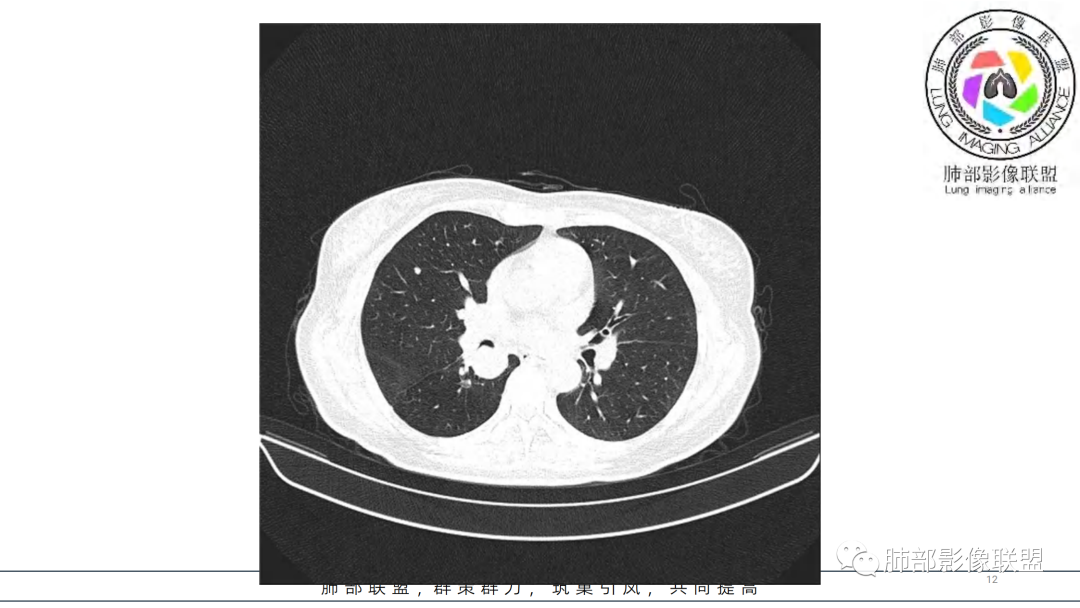

2.右肺下叶及中间段支气管后方类圆形块影,边界较清楚,未见分叶及毛刺,病灶部分突入支气管腔内(冰山一角),局部管腔狭窄,相应肺叶未见片影或体积变化。

3.块影密度均匀,未见液化坏死及钙化,渐进性强化,强化显著。

中青年女性,支气管管腔内外肿块(“冰山征”),边界较清楚,强化显著,未见阻塞性肺不张,尽管未出现“类癌综合征”临床表现,仍然符合典型类癌影像学表现。

类癌临床表现无特异性,影像学检查仍然是肺类癌的主要诊断依据。其特征性表现是孤立的、边界清楚的肿物,密度可均匀或不均匀,边缘多清楚锐利,部分病例可见浅分叶及毛刺。类癌侵及的支气管局部增厚,与正常的管壁分界清楚,局部呈乳头状突起,表面光滑。肺门旁肿块往往边缘光整、轮廓清楚、密度均匀,增强扫描大多呈均匀明显强化,可有持续强化或延迟强化。中央型肺类癌可引起支气管壁局限性增厚,形成轮廓光滑的管壁结节,并与腔外大病灶形成“冰山征”。少数病例可沿支气管腔内长轴生长,呈指套样改变,类似肺鳞癌,但较肺鳞癌血供丰富。